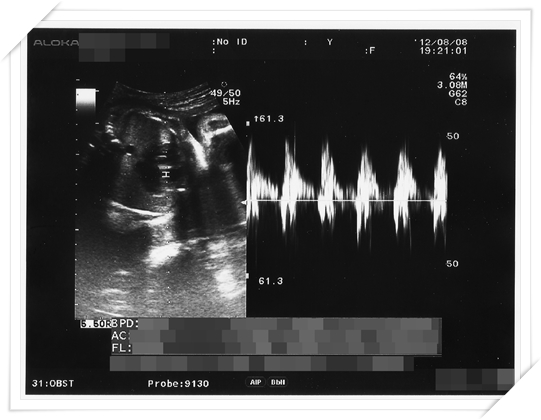

Week 30

這個星期又到了我們例行產檢的時候啦

接著 照完超音波 一切正常之後

醫生看看我 又再低頭看了看剛才印出來的超音波報告

就回答我說“恩 是胖的有比較快啦 但是小朋友也長了一公斤阿!”

於是我就說“(指小鴨胖了一公斤) 那這樣是還好嗎?”

醫生就笑笑跟我說“我可沒有說喔!”

意思就是 小鴨你真的胖太多了吧!!!!!!!!!!!!!!!!!!!!!!!!!!!!

這個時期 其實baby 的體重應該要少個三四百克以上的

但是不知道是我吃得太營養 還是小鴨太會吸收 一個月體重就往上飆了快一公斤

更何況我才七個多月耶

再這樣下去 小鴨真的會變巨嬰啦!!!!